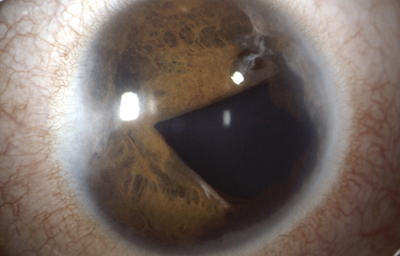

Diastasis: Significa la presencia de agujeros en la raíz del Iris parecidos a una Iridodiálisis

Diastasis del Iris: en un caso de Atrofia Esencial del Iris (Síndrome ICE)

Archivo Fotográfico Dr. Francisco Barraquer